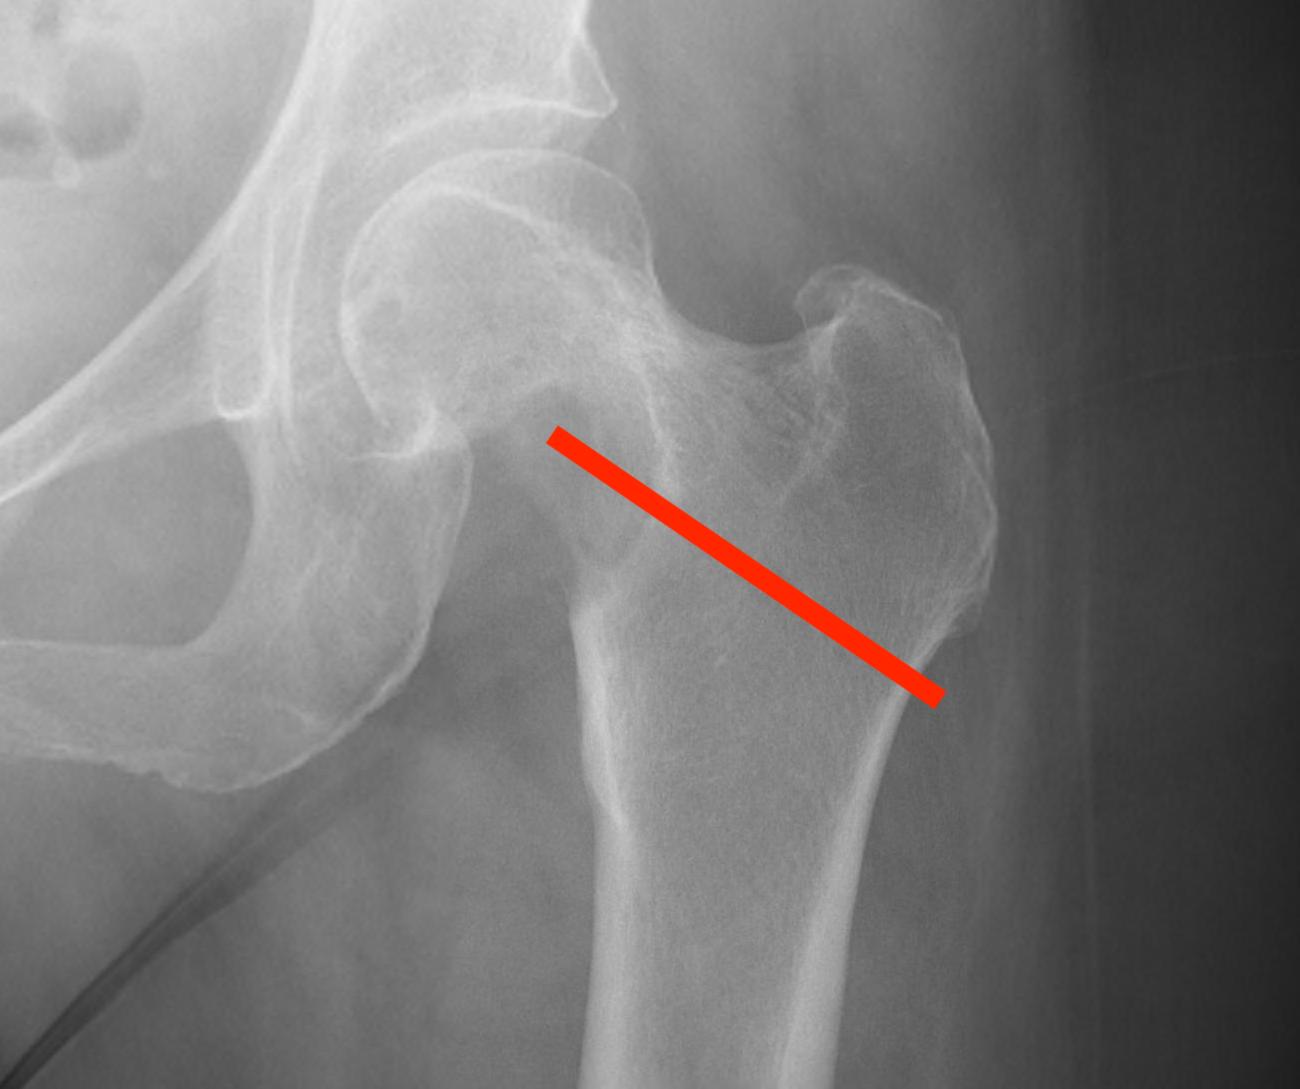

1.  Femoral head / neck

- lateral approach

- trans trochanteric

- avoid NV bundle and quadriceps

Proximal Femur TumourProximal femur biopsyFem neck biopsy